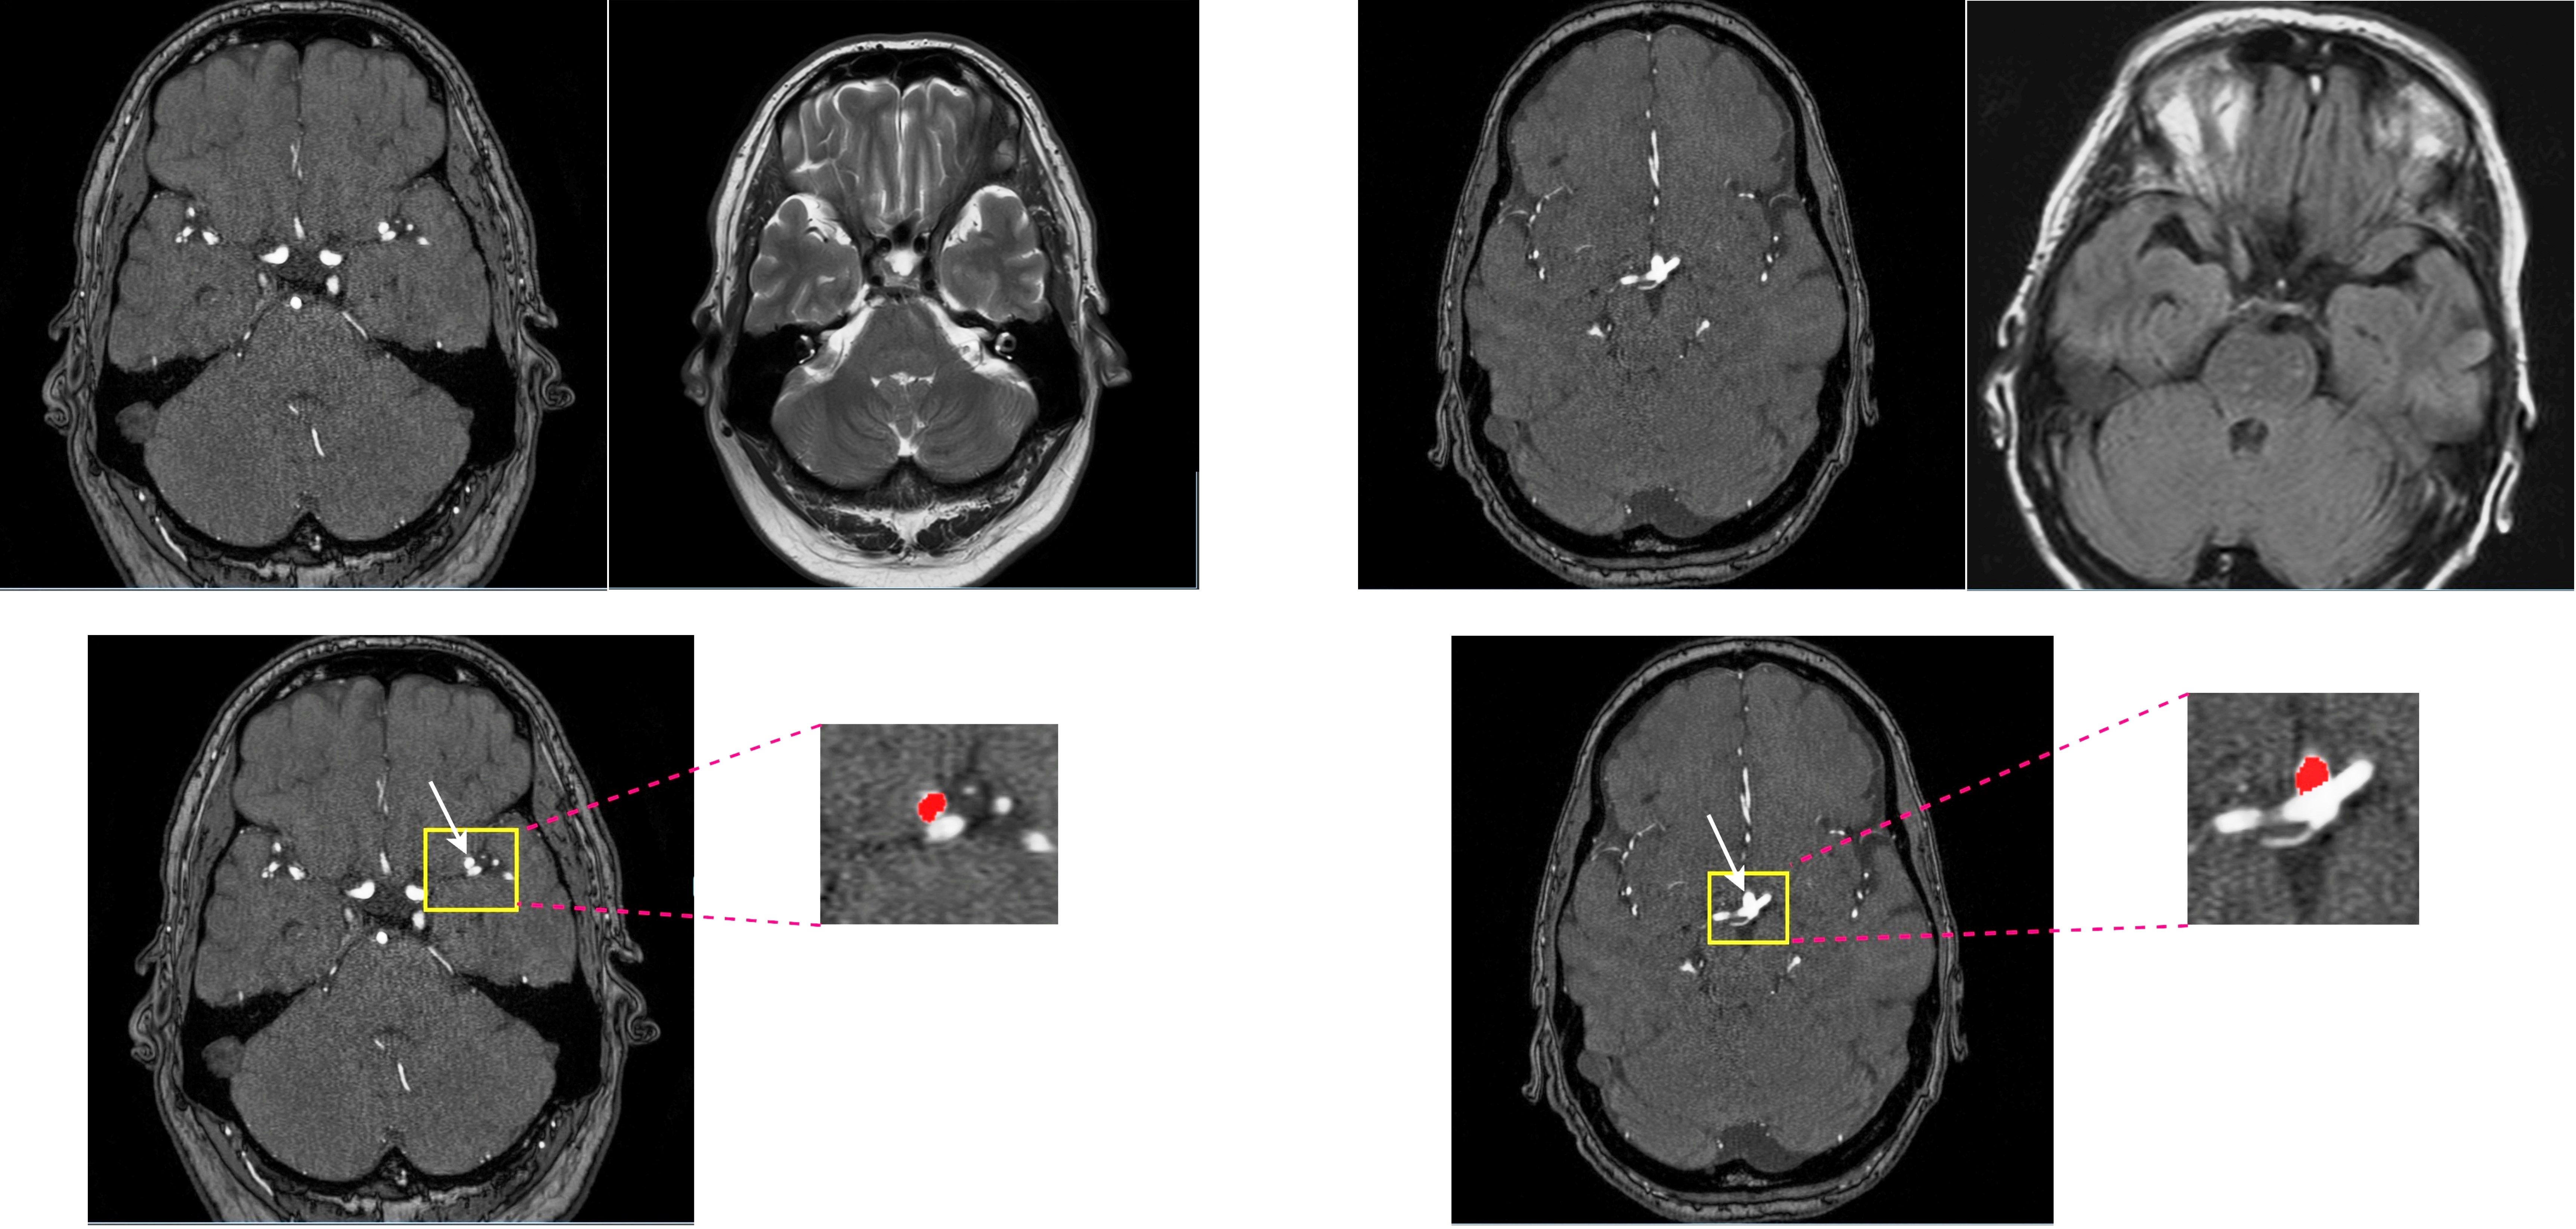

We used the ADAM dataset composed of 113 TOF-MRA and structural MRI (93 patients with unruptured intracranial aneurysm [UIAs]) [4]. The total number of UIAs was 125 and the voxel-wise annotations were drawn in the axial plane by two radiologists. All MRIs were performed at the UMC Utrecht, the Netherlands, on a variety of Philips scanners with field strength of either 1.5 or 3T. The TOF-MRAs had an in-plane resolution of 0.2 to 1 mm and slice thickness range of (0.4–0.7) mm, without a set acquisition protocol. Two cases of ADAM are shown in Figure 1. To automatically detect and localize the intracranial aneurysms in ADAM dataset, a 3D full resolution of nnDetection deep learning model was employed. The nnDetection framework uses the Retina U-net [5] architecture that combines the Retina Net detector with the popular U-Net segmentation model. In Retina Net as a one-shot detector, classification and bounding box regression tasks are directly performed using the intermediate activation maps from the output of each decoder block in the Feature Pyramid Network (FPN) [5]. Figure 2 shows an overview of the detection model and Retina U-net architecture. In addition, while Retina U-Net uses a loss function consisting of pixel-wise cross entropy loss [6] and soft Dice loss [5] for segmentation, binary cross entropy (BCE) and generalized intersection over union (GIoU) [7] were used for classification and box regression respectively. Like nnU-Net, the nnDetection runs some preprocessing techniques including cropping, Z-Score normalization, and scaling. The patch size is decreased while adapting the network architecture and the batch size is fixed to four. Retina U-Net with an encoder which consists of plain convolutions, ReLU and instance normalization blocks. We ran the model for 100 epochs with 2500 mini batches per epoch and applied five-fold cross validation. To update the network’s weights, SGD with Nesterov momentum 0.9 is used. We trained all the models 3* RTX 3090 GPU with patch size of 256 × 224 × 56.

Figure 1. Left: case 22, aneurysm 3D coordination: (353, 230, 78). Right: case 78, aneurysm 3D coordination: (268, 262, 54) from ADAM dataset.